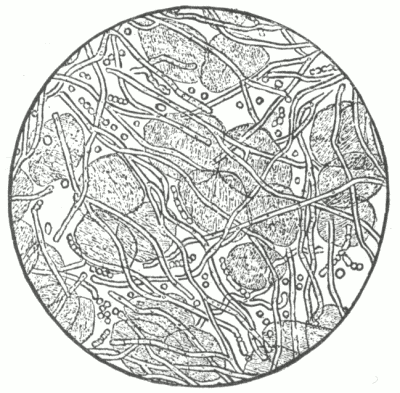

Fig. 3.

C, epidermis; D, corium; P, papillæ; S, sweat-gland duct.

v, arterial and venous capillaries (superficial, or papillary plexus) of the papillæ.

Deep plexus is partly shown at lower margin of the diagram; vs—an intermediate

plexus, an outgrowth from the deep plexus, supplying sweat-glands, and

giving a loop to hair papilla.

(After Ranvier).

Fig. 4.

a, a vascular papilla; b, a nervous papilla; c, a blood-vessel; d, a nerve fibre;

e, a tactile corpuscle.

(After Biesiadecki.)